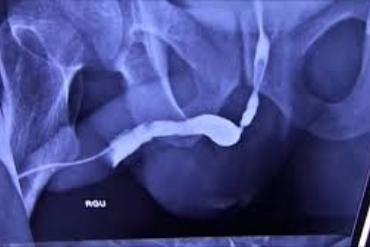

Urethral Stricture

Specialized treatment for narrowing of the urethra.